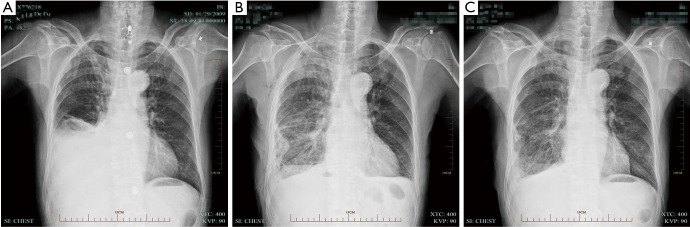

Efficacy was evaluated according to conventional criteria (10): (I) complete recovery (CR) was reflected by effusion clearance lasting for more than 4 weeks; (II) partial recovery (PR) indicated effusions reduced to less than 50%, lasting for more than 4 weeks; CR and PR represented effective treatment. After IPTC, 54 cases showed CR, and 2 had PR; pleural effusion was controlled in 100% of patients. Symptoms, including chest distress, shortness of breath, cough, and chest pain, were noticeably ameliorated. KPS scores were increased in 48 cases (88.9%) (Figure 1).

Figure 1.

Chest X ray showing pleural effusion under control in 100% of patients. (A) Before IPTC; (B) two months after IPTC; (C) six months after IPTC. IPTC, intrapleural perfusion thermo-chemotherapy.